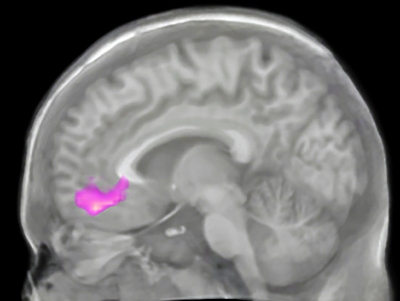

Os resultados da ressonância magnética funcional, que mede o metabolismo do oxigênio nas células cerebrais ativas, mostraram que a atividade relacionada ao altruísmo aumenta no córtex pré-frontal ventromedial, uma área profunda no cérebro associada ao altruísmo em estudos anteriores.

“Descobrimos que a atividade registrada no córtex pré-frontal ventromedial mudou nas pessoas no grupo de reconhecimento da gratidão,” disse Karns.

“Este grupo como um todo teve um aumento no sinal com relação ao ganho de dinheiro pela instituição de caridade em relação a assistir elas próprias ganhando o dinheiro, como se elas fossem mais generosas para com os outros do que para com elas mesmas”.

Os resultados indicaram que a parte do cérebro que dá suporte ao sentimento de recompensa é flexível, permitindo mudanças nos valores de uma “moeda neural” associada aos sentimentos de altruísmo.